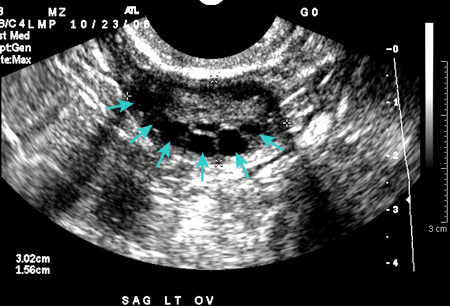

Polycystic ovarian ultrasound

From the collection of Dr M. O. Goodarzi; used with permission

See this image in context in the following section/s:

Polycystic ovary syndrome